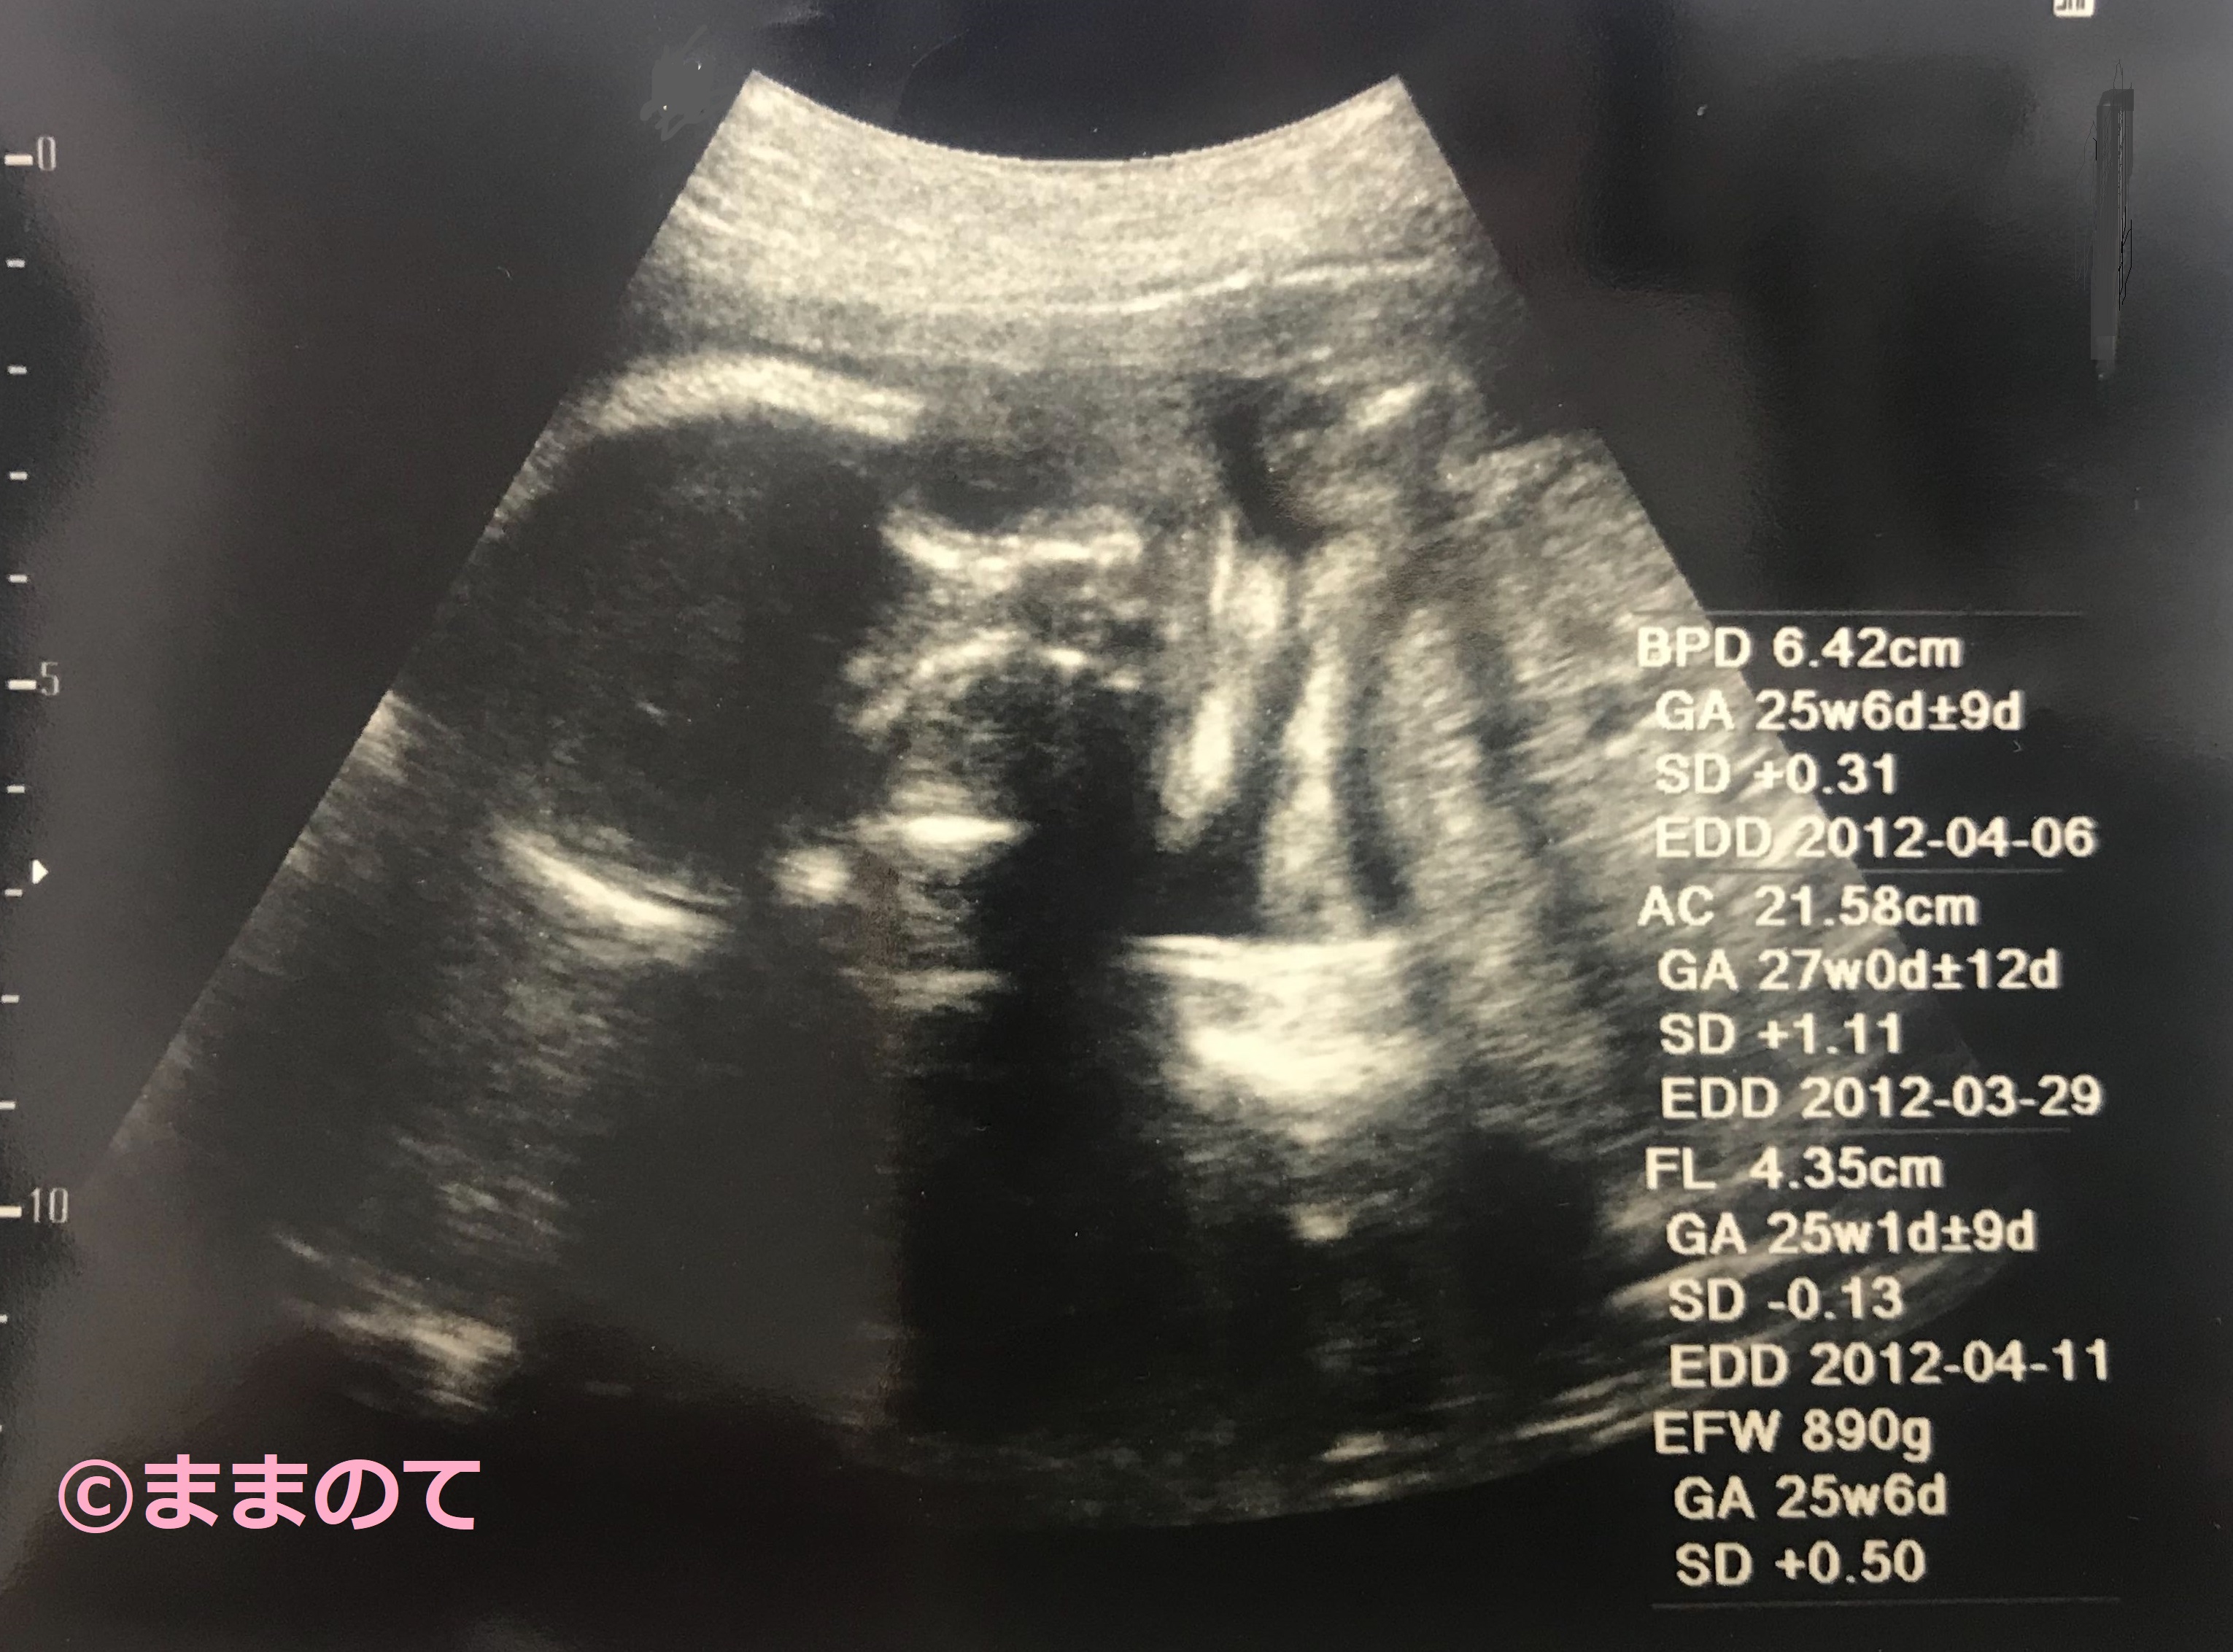

妊娠27週のエコー写真